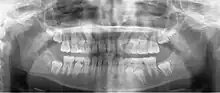

A dental panoramic radiograph, showing the maxilla and mandible, all the teeth including the "wisdom teeth," the frontal and maxillary sinuses, the nasal cavity and the temporomandibular joint and other near by head and neck anatomy. | |

A panoramic radiograph is a panoramic scanning dental X-ray of the upper and lower jaw. It shows a two-dimensional view of a half-circle from ear to ear. Panoramic radiography is a form of focal plane tomography; thus, images of multiple planes are taken to make up the composite panoramic image, where the maxilla and mandible are in the focal trough and the structures that are superficial and deep to the trough are blurred.